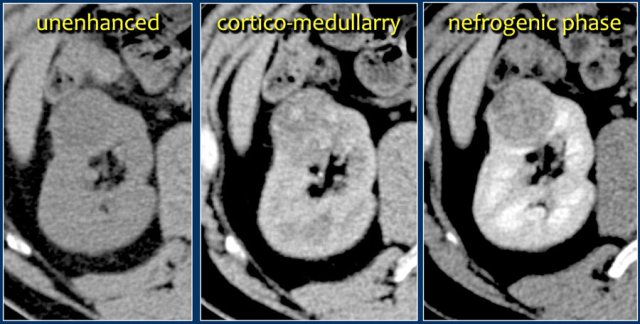

Here is another case.

In the nephrogenic phase one could argue there is a lesion in the left kidney.

In the corticomedullary phase however it is clear that this is a pseudotumor.

The corticomedullary phase 25-40 sec post injection is strongly recommended. It helps to differentiate tumor from pseudotumor and to assess enhancement of a lesion.

In this phase however a tumor located in the renal medulla can have the same attenuation as the surrounding parenchyma (figure).

Therefore the nephrogenic phase (±100 sec post injection) is the most important phase for the detection of a tumor.